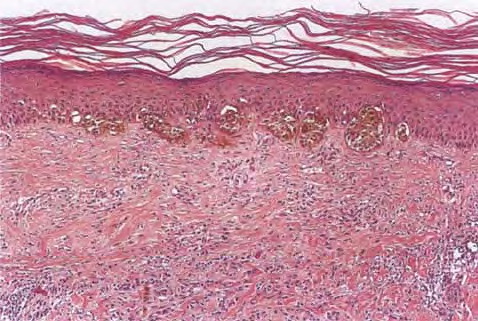

Recurrent nevus phenomenon = ظاهرةالوحمة الناكسة